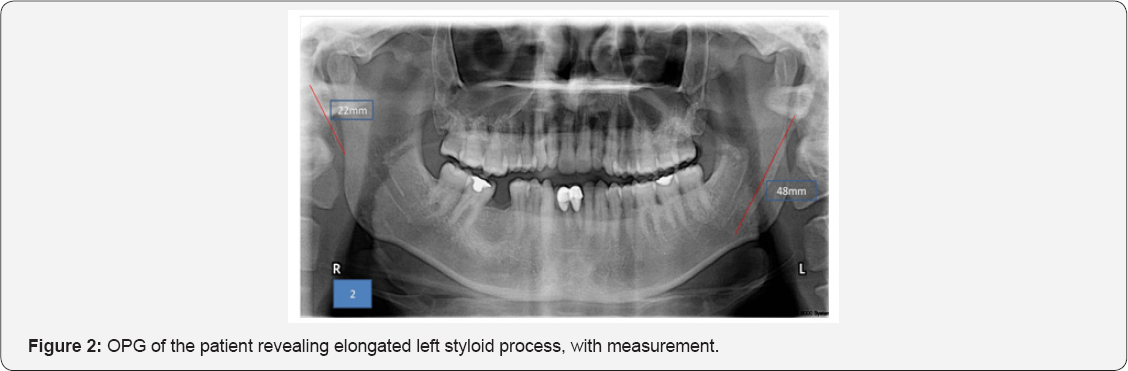

Based on the history and clinical findings, a provisional diagnosis of Myofacial Pain Dysfunction Syndrome was put forth. And Eagles syndrome was considered under differential diagnosis. Panoramic radiograph showed that the length of left styloid process to be 48mm, with Langlais type I pattern (Figure 2). Considering the elongated styloid process and suspecting eagle's syndrome, CBCT was advised. CBCT scan showed unilateral elongation of the styloid process towards the left. The actual length of the styloid process was processed using CBCT in various sections (Figure 3A-3D), and was found to be 62.2mm in comparison with the OPG, which was 48mm. Almost a difference of14mm was noticed between the two modalities. Hence showing, CBCT as the most reliable radiologic modality, to be carried out in cases where styloid process elongation is suspected. Based on the history, clinical findings and investigations, a final diagnosis of Eagles Syndrome was given and the patient was referred, for the removal of the styloid process.

a) Type I (Elongated styloid process) pattern that represents an uninterrupted, elongated styloid process, which is reported in our case.